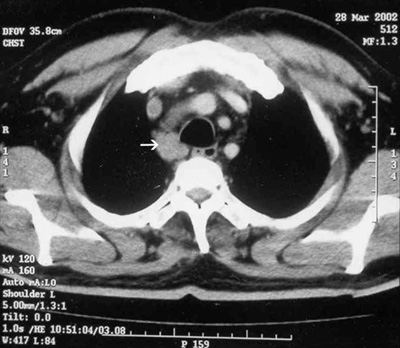

Results of routine tests (including biochemical, haematological and liver function tests) were all normal except for a raised erythrocyte sedimentation rate (65 mm/hour). Indirect laryngoscopy performed to investigate the hoarseness revealed paralysis of the right vocal cord with no other local abnormality. The palate showed normal mobility and the bilateral gag reflex was normal. A chest x-ray showed clear lungs, with some mediastinal widening. A computed tomography scan of the thorax revealed enlarged mediastinal lymph nodes (Box 2).

After two weeks' treatment with prednisolone 1 mg/kg per day, the patient's rash had resolved completely and the hoarseness was markedly reduced. A repeat computed tomography scan of the chest done after four weeks of treatment showed that the mediastinal lymph nodes had decreased in size. The patient has remained asymptomatic over seven months of follow-up.